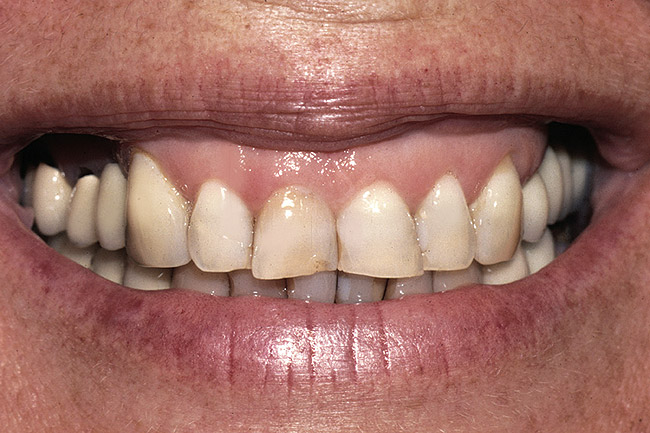

Figure 6  A patient presented with severe anterior wear and over-eruption. Esthetically, the maxillary centrals needed lengthening by 3 mm incisally.

Figure 6

Figure 7  A full-arch temporary was placed to correctly identify an acceptable incisal edge position prior to surgery.

Figure 7

There are several methods for identifying the correct incisal edge position pre-surgically, including the use of an overlay matrix, altering the contour of the existing teeth using reshaping or bonding, and preparing the teeth and placing temporaries.15 The patient who almost always requires tooth preparation and temporaries in order to correctly identify the incisal edge position is the one with severe wear and a need for the addition of significant length to the incisal edge of the existing teeth. Because there are such significant functional concerns in altering the incisal edge position of these patients, using a simple removable overlay to identify the esthetic position of the incisal edge and gingiva is risky. Instead, it is much more predictable to lengthen the teeth temporarily to evaluate the esthetic and functional success of the new incisal edge position prior to any crown lengthening. If the teeth are amenable to direct bonding to alter incisal edge position, this is often the best approach to temporization. If, on the other hand, the teeth are severely worn and bonding is not realistic, it will probably be necessary to prepare them and place temporaries to evaluate the change. Once it becomes clear that the new incisal edge position is acceptable both esthetically and functionally, the periodontal surgery can be completed to correct gingival levels and, therefore, crown length (Figure 6, Figure 7, Figure 8, Figure 9 and Figure 10).